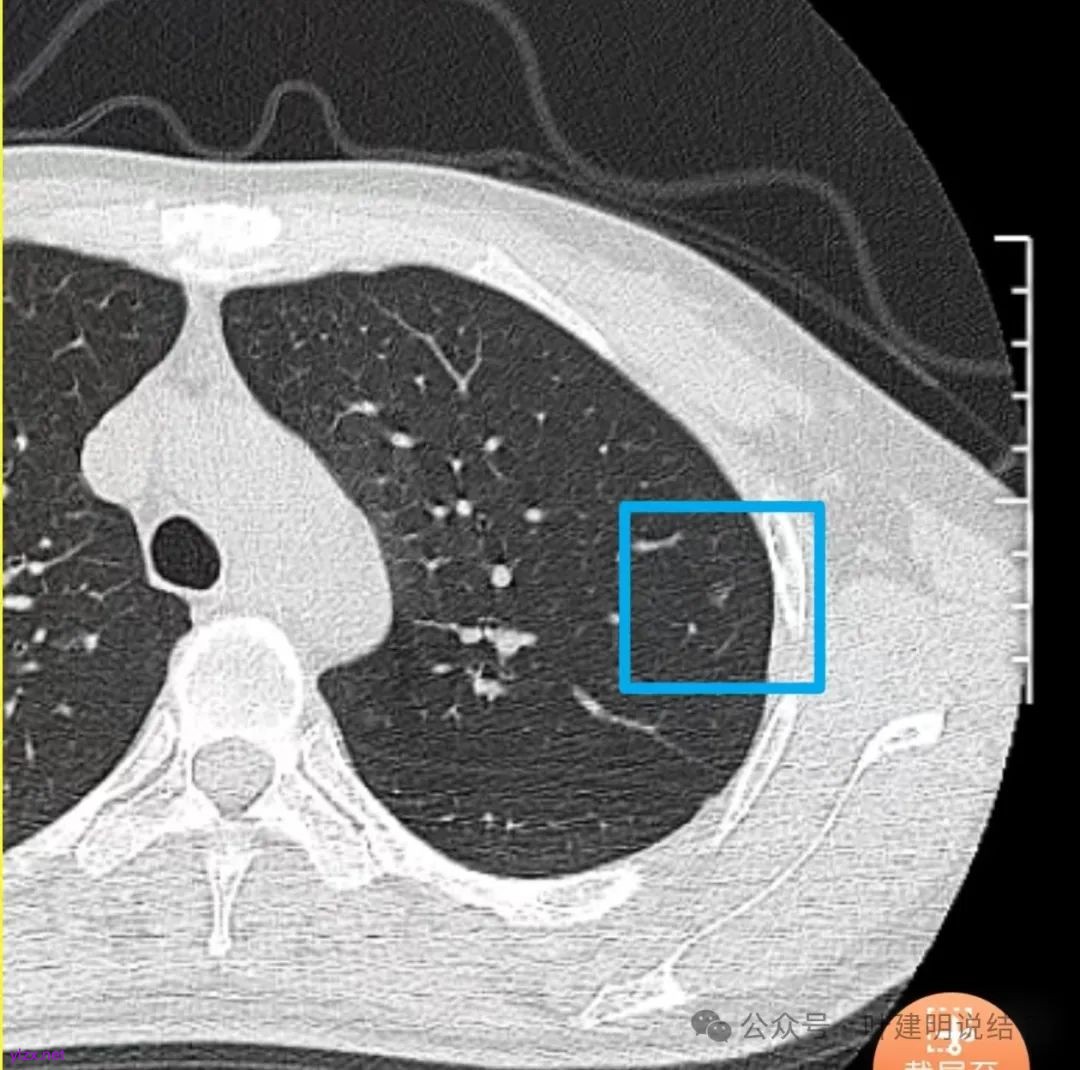

先来看2024年12月的影像:

在上叶淡而轮廓较清,密度不太纯略显杂乱的小磨玻璃结节。

右下叶磨玻璃结节伴空泡征,轮廓较清,瘤肺边界清楚。

表面不平,轮廓较清,有血管进入,边缘略显毛糙。

病灶内有少许偏实性成分,与血管关系较为密切,局部似有浅分叶的样子。

两肺多发结节,左侧黄色标注的考虑是肺泡上皮增生可能性大;蓝色的考虑肺泡上皮增生或者少许慢性炎可能性大;右侧红色宽起来并带有红色箭头的这处是主病灶,偏混合密度,整体轮廓较为清楚,边缘显得毛糙,从2024年12月份的来看,要考虑是肿瘤范畴,原位癌或者微浸润性腺癌可能性较大,也不能完全排除不典型增生。但是在2022年的时候,这个病灶的边上也有一个实性的微小结节,如果只看2022年的,这么小的实性结节,又比较圆,表面也显得较为光滑,是要考虑良性的,当然太小了需要动态观察。回头再重新来看2024年底的,发现绿色箭头所指的这个微小实性的较2022年几乎没有变,去仔细寻找2022年的,发现当时在实性结节旁边也有密度很淡的一点磨玻璃影(也可能真的就是一处,只是扫描不够薄,密度的变化有些突兀而已),而到了2024年12月份,实性微小这处没有明显变化,但是原来很淡的磨玻璃变成了混合磨玻璃,范围也明显扩大。所以总体来看右肺下叶这处是考虑恶性的,而且从磨玻璃结节角度来讲,还是生长比较快的,就是说还是有一定风险的。加上左侧还有两处也是磨玻璃持续存在,虽然边缘轮廓显模糊一点,但多年以后也可能仍然要变成原位癌或者微浸润性腺癌之类的东西。通盘考虑以后,我倾向于右侧近期单孔胸腔镜下微创局部切除,左侧随访观察,等到有进展并风险增加再来考虑处理。意见供参考!